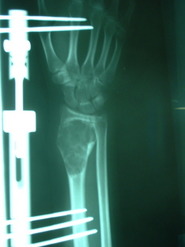

Paciente del sexo femenino de 15 años de edad, portadora de Quiste Óseo Aneurismático de radio derecho, quien había sido intervenida hace aproximadamente 1 año en otro centro, donde le practicaron curetaje de la lesión y relleno del quiste con injerto de cresta ilíaca. La lesión recidiva, acude por la consulta del Dr. Alberto A. Martínez Conde, donde previa revisión de las laminas histológicas por parte del Dr. David Mota, se practicó curetaje amplio del quiste y relleno de la cavidad con Hidroxiapatita sintética e injerto de cresta ilíaca, se estabilizo el radio con tutor externo.

El resultado post-operatorio con seguimiento de 1 año fue excelente, sin signos de recidiva